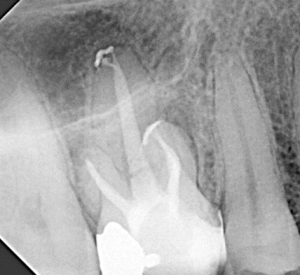

Root Canal / Retreatment

Clinical Cases